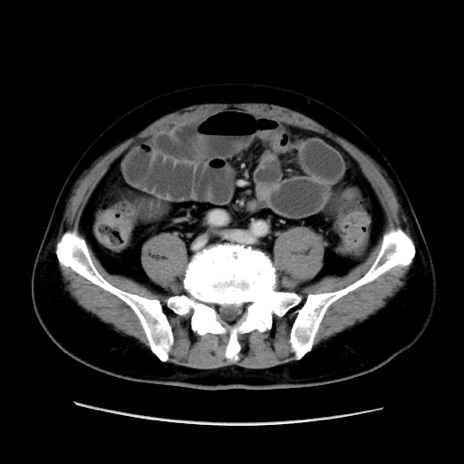

症例16(横断像)

【症例】 70歳代男性

【主訴】 腹痛、嘔吐

【現病歴】 約1ヶ月前より間欠的に腹痛と嘔吐あり、当院消化器内科を受診したところCTで多発する肝臓のLDAを指摘され、精査中であった。以降は消化器症状は安定していたが、2日前より嘔気と腹痛があり、同日より排便・排ガスが消失した。改善認めず、 本日、救急外来を受診した。

【身体所見】意識清明・会話良好、BT 36.3℃、BP 127/80mmHg、 P 80bpm、腹部:膨満あり、平坦・軟、上腹部正中および下腹部正中に圧痛あり、反跳痛なし、筋性防御なし。

【データ】WBC 7200、CRP 0.77